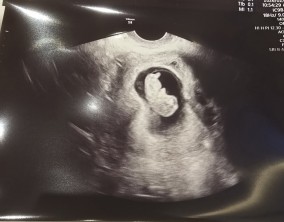

첫째·둘째 모두 갓핸드의 선물